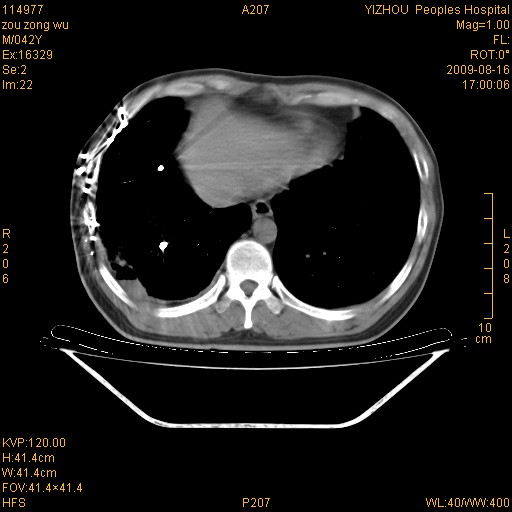

以下是引用zjzjr在2009-8-17 10:42:00的发言:[br]右侧间质性肺炎伴纤维化,右肺下叶肺囊肿伴感染(不除外外伤后引起),右肺野及胸壁软组织\\肝内见多发斑点状,中枪了吧.右侧胸膜肥厚\\粘连.